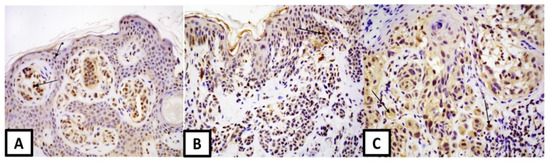

2.3. Immunohistochemistry

2.4. Assessment of Immunostaining